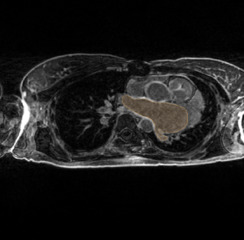

Revision as of 00:24, 9 January 2012 by Ggardner (talk | contribs) (An example of a hypertrophied LA, the extent of which is denoted by the orange label mask.)

An example of a hypertrophied LA, the extent of which is denoted by the orange label mask.